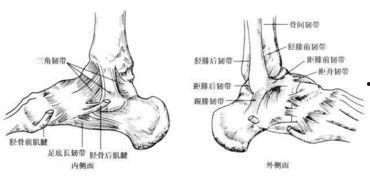

三、脚踝韧带撕裂的图片展示

下面是一些真实的脚踝韧带撕裂图片,让你直观地了解这种损伤。

1. 轻度撕裂:图片中可以看到,脚踝周围的韧带只有轻微的断裂,但仍有部分连接。

2. 中度撕裂:这种撕裂的韧带断裂面积较大,但仍有部分连接。

3. 重度撕裂:韧带完全断裂,断裂处可见明显的缝隙。